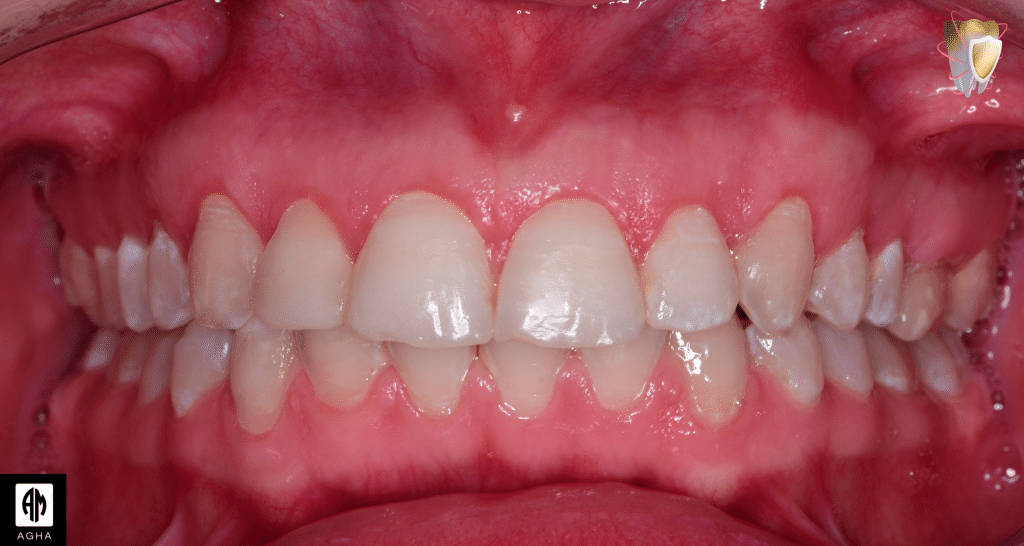

1 month follow up showing correction of gummy smile

Intra oral photo showing harmony of gingival margins

Rechecking the distance during smile after 1 month follow up showing that it was reduced from 4mm to 1mm